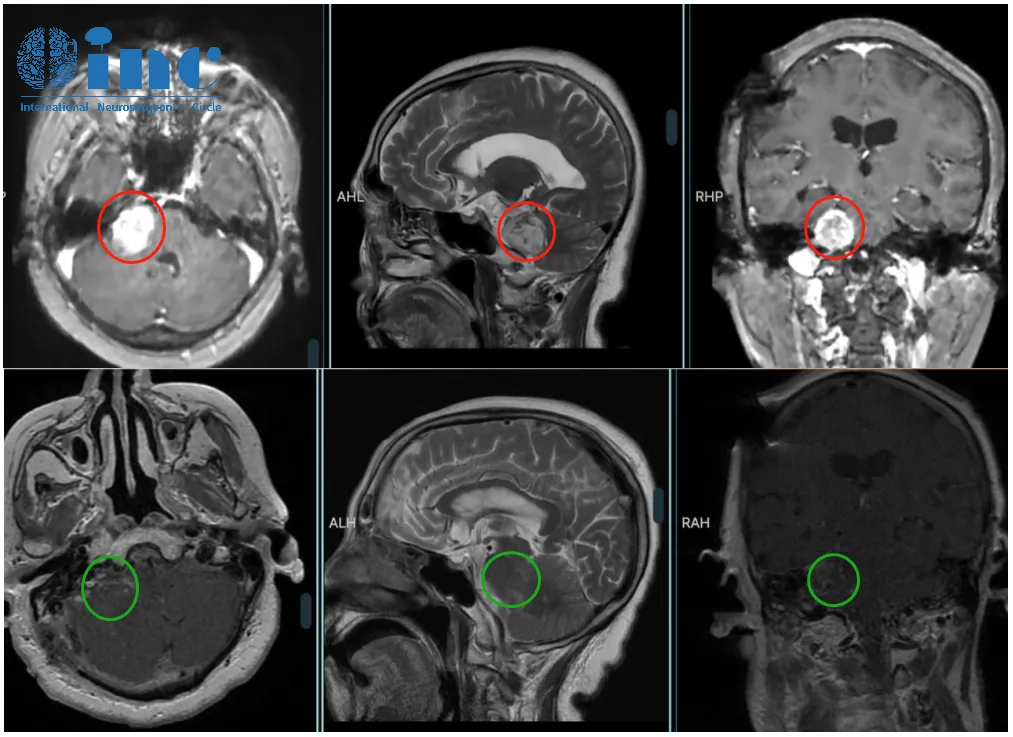

78岁女性患者李奶奶(化名),听神经瘤确诊一年内肿瘤快速生长至3厘米以上,属大型听神经瘤。病情进展伴随严重临床症状:听力水平显著下降、脑积水、行走不稳及下肢无力等,健康状况受到严重威胁。

巴特朗菲教授详细评估影像学资料后指出:虽然放射外科治疗可行,但针对该尺寸肿瘤,长期控制效果可能欠佳。放疗后3-4年肿瘤可能继续生长需手术治疗,届时患者年龄超过80岁,手术风险显著增加。因此推荐实施肿瘤全切术,避免术后复发风险。

2022年巴特朗菲教授在华学术交流期间,为患者实施听神经瘤显微切除术。手术实现肿瘤全切,神经功能保护良好。术后一年随访显示,患者恢复状态良好,神经功能保持正常。